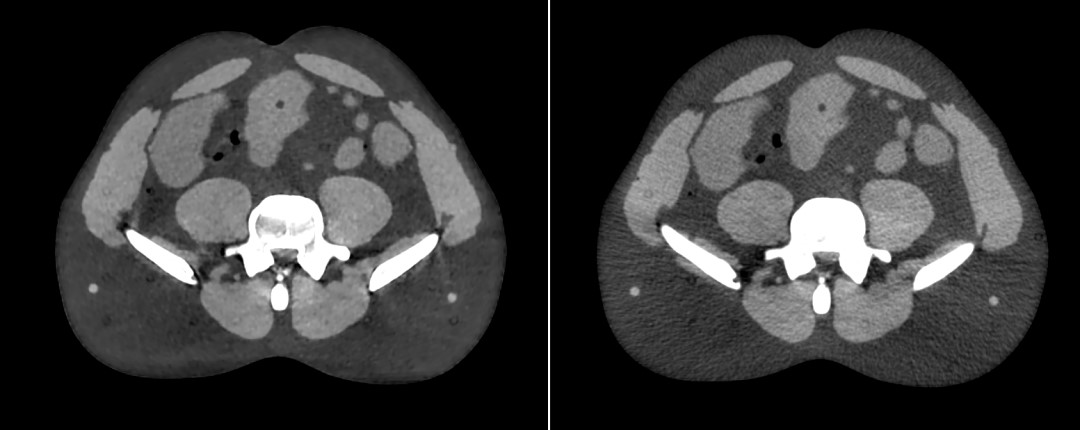

图3为本科室一头颈部病例在Head模式下iCBCT图像和标准模式kV CBCT图像的对比图,图4为使用成年男性CRIS模体Pelvis扫描模式下iCBCT图像和标准模式kV CBCT图像的对比图。自全新一代Halcyon加速器在本科室应用以来,其iCBCT技术带来的图像质量的提高,得到了医生、物理师和放射治疗师的认同。

(左图)iCBCT图像 / (右图)标准模式CBCT图像

图4 CRIS腹部模体Pelvis扫描模式下CBCT图像对比